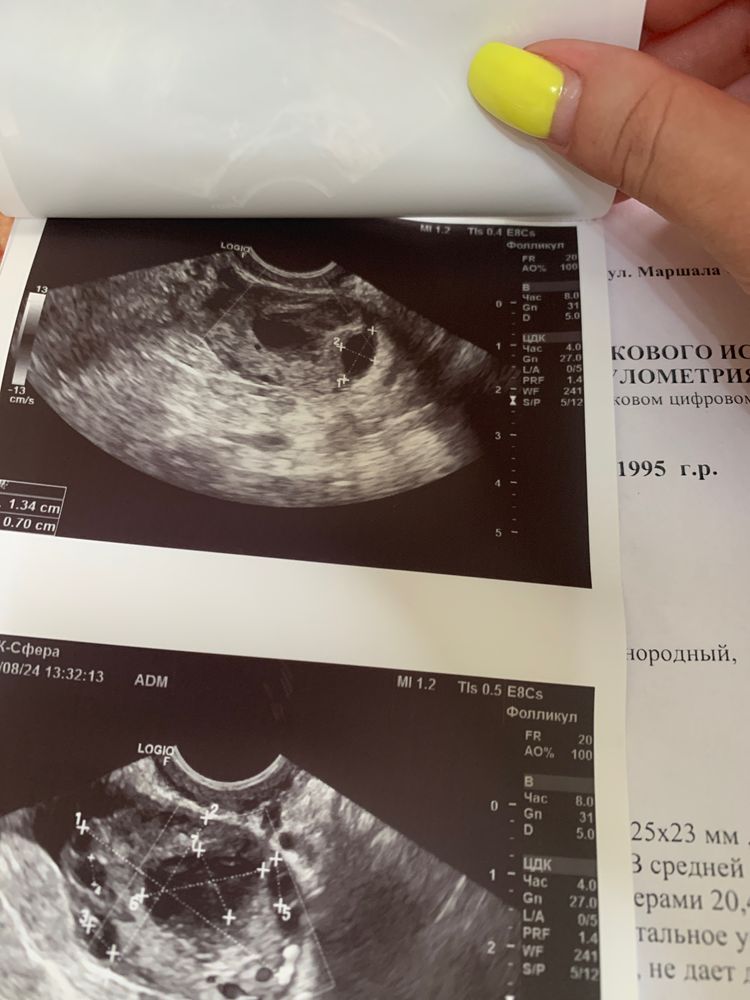

Фолликулометрия

Вот такие результаты узи ,вроде есть желтое тело ,или это с того цикла помогите расшифровать ,так же мне сказали у меня лопнула киста и остались остатки от нее ,меня недавно реально сильно прихватило,видимо тогда и лопнула ,правый яичник посмотреть не смогли